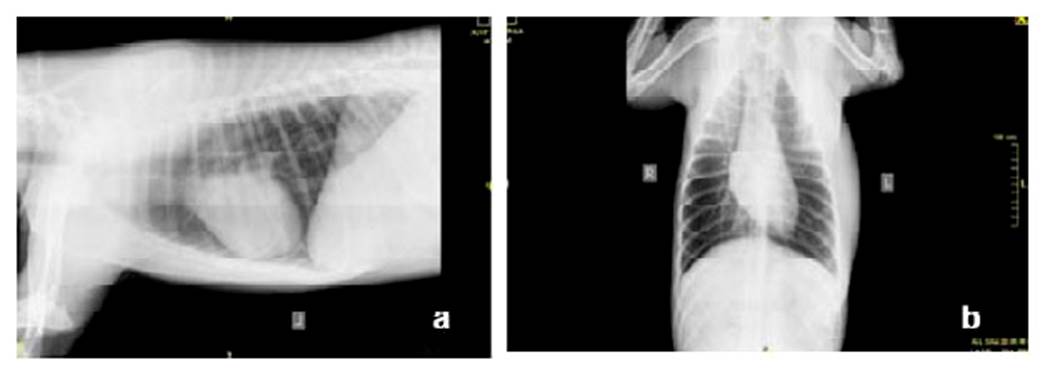

Con base en la información obtenida en la historia médica y el examen físico, se estableció como diagnósticos diferenciales trauma de tejidos blandos por contusión de segundo grado y absceso. Se procede a realizar cuadro hemático (Cuadro 1), radiografía de tórax laterolateral y ventro-dorsal (Figura 2).

Las radiografías de tórax (Figura 2) evidencian aumento de tamaño en tejido blando de zona costo-axilar izquierda, sin evidencia de lesión en cavidad torácica.

Figura 2 Radiografías vistas a) laterolateral y b) ventro-dorsal de tórax de canino Siberian Husky de 10 meses